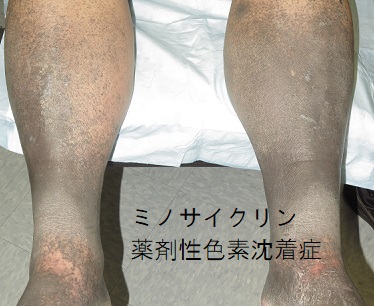

薬剤性色素沈着症